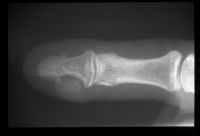

Case 5.

Distal phalanx osteochondroma. This painless unusual benign tumor resulted in a severe nail plate concavity.

Highslide

Excision.

Restoration of normal nail plate contour.